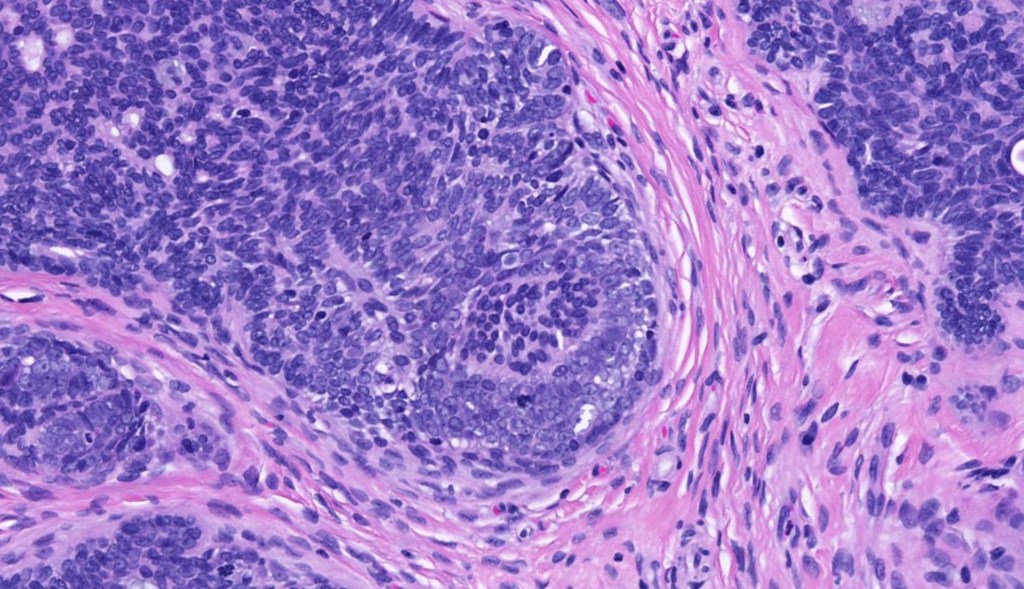

•The classical appearance consists of keratocysts & lobules of basaloid cells

•Basaloid lobules show peripheral palisading

•Perifollicular mesenchyme is always conspicuous and sometimes densely aggregated are seen indenting the baslaloid lobules (papillary mesenchymal bodies)

Trichoepithelioma should be distinguished from trichoblastoma since the latter is very rarely syndromic. Trichoepithelioma is largely a dermal tumor whereas trichoblastoma often extends from the dermis into subcutaneous fat or deeper in very large examples. Papillary mesenchymal bodies are much better formed and generally more obvious in trichoepithelioma. Trichoepithelioma must also be distinguished from basal cell carcinoma. Retraction artifact & stromal mucin are features of basal cell carcinoma and not trichoepithelioma. Papillary mesenchymal bodies are not seen in basal cell carcinoma.